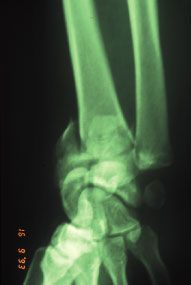

Congrès - Compte rendu Ostéotomie précoce des cals vicieux articulaires de l'extrémité distale du radius , Ph. Saffar Institut Français de Chirurgie de la Main - France , S. Romano Institut Français de Chirurgie de la Main - Paris N°122 - Mars 2003 ● 10 min de lecture